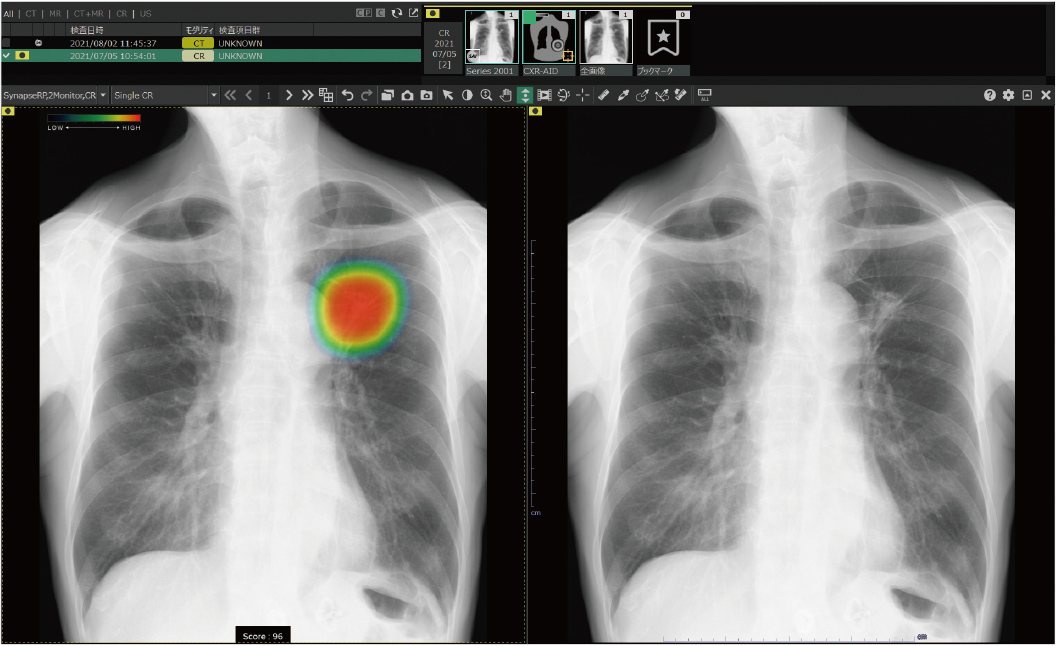

胸部X線画像病変検出ソフトウェア CXR-AID

胸部X線画像を自動解析。病変の存在が疑われる領域を検出・マーキングし、見落し防止します。